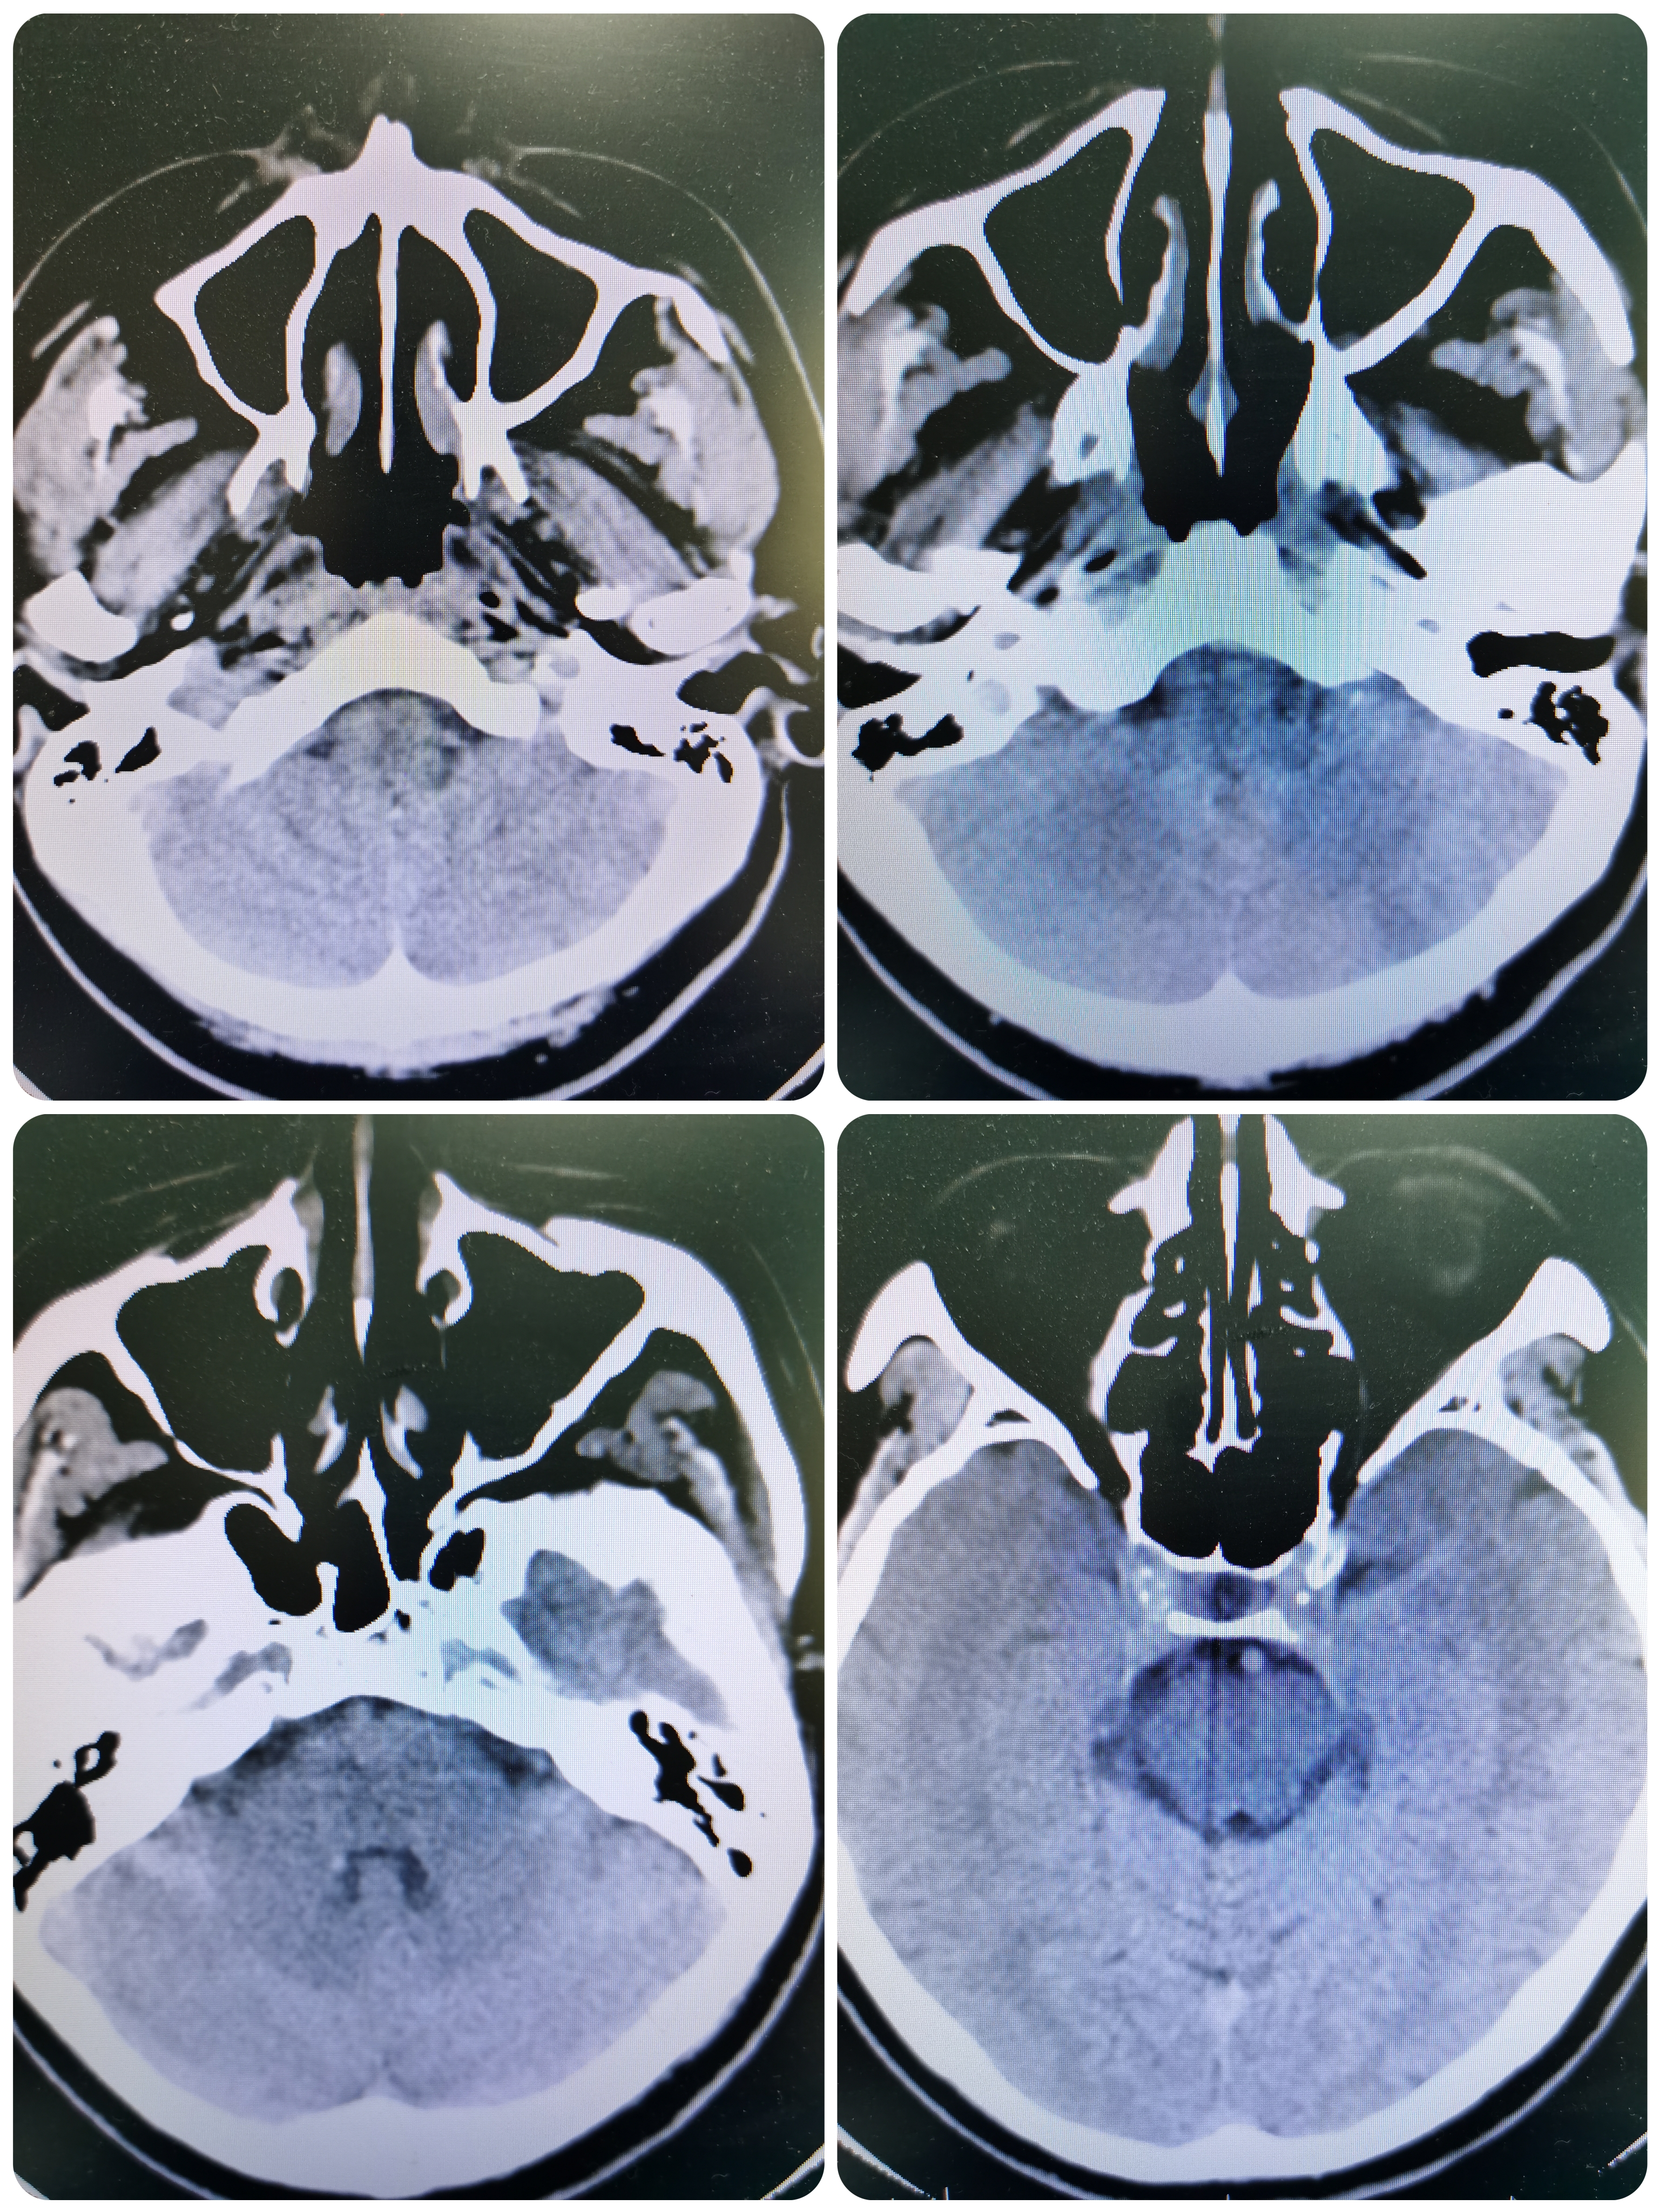

1、本例患者临床表现为头晕,恶心,呕吐后循环缺血症状,急诊CT除外出血后给予静脉溶栓治疗。经内科治疗后症状逐渐改善。但患者无卒中高危因素,需完善脑血管相关检查。

2、CTA证实左椎动脉起始部重度狭窄合并血栓,系责任血管,存在急性闭塞或残存血栓脱落至基底动脉风险,需积极处理。